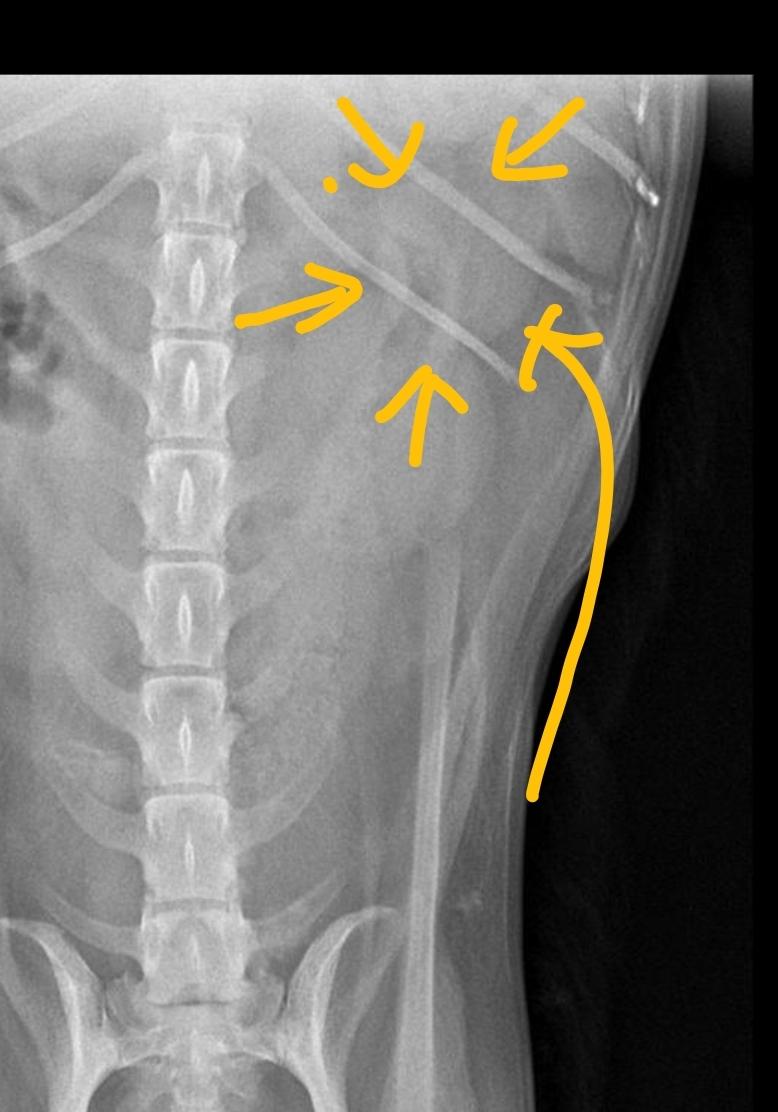

10년된 강아지가 아파서 밥도못먹고 낑낑대고 다리도 절뚝거리고하는데 병원가서 검사도 받고 다했는데 괜찮다고하네요 근데 x-ray사진을 봤을때 제가봐도 이상하고 다른사람들이 봐도 이상하다고 보는데 왜 의사만 괜찮다고 할까요?? 혹시 사진보시고 뭐가 문제인건지 알 수

있을까요??

해당 부위에 종괴가 있는것으로 보이니 정밀 초음파 검사나 CT촬영이 가능한 동물병원에 데려가서 다시 검진 받으시기 바랍니다.